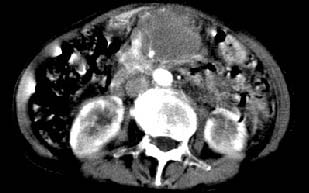

ct:肝胃之间、胰头后、腹主a周围,融合而成团块状影,包绕血管,胰腺前移后缘分界欠清,与肝胃分界清,肿块未见明显强化,肝右叶后段小囊肿。

胰腺受压前移,胰管扩张,应为腹膜后占位,病灶密度不均,有低密度坏死区,强化扫描强化不明显腹腔干动脉受侵,考虑腹膜后恶性占位

肝胃之间、肝十二指肠韧带,胰头后、腹主a周围,融合而成团块状影,包绕血管[腹腔干、肠系膜上动脉,腹主动脉],胰腺前移后缘分界欠清,与肝胃分界清,肿块未见明显强化,肝右叶后段小囊肿。

主动脉-胰腺间隙可见巨大分叶状软组织肿块影,包绕腹主动脉、腹腔干及其分支、腔静脉等大血管,增强呈无明显强化,临近脏器明显受压移位,增强示有分界。肝右叶可见局限性低密影,边缘清楚。

再看从肠系膜根部到胰腺后主动脉及上腔静脉周围可见相连的较大的软组织肿块影,形态不规则,呈明显

的大小不等的分叶状,其中密度较均匀但其中可见条状低密度区,肿块边缘比较清晰周围的小肠受压移位

明显且堆积。

增强所见,腹腔动脉,肠系膜上动静脉被肿块包绕,结合平扫的条状低密度区恰好位于血管周围,较大的

肿块强化不明显(遗憾的是没有标上ct值)但胃壁强化的十分明显。